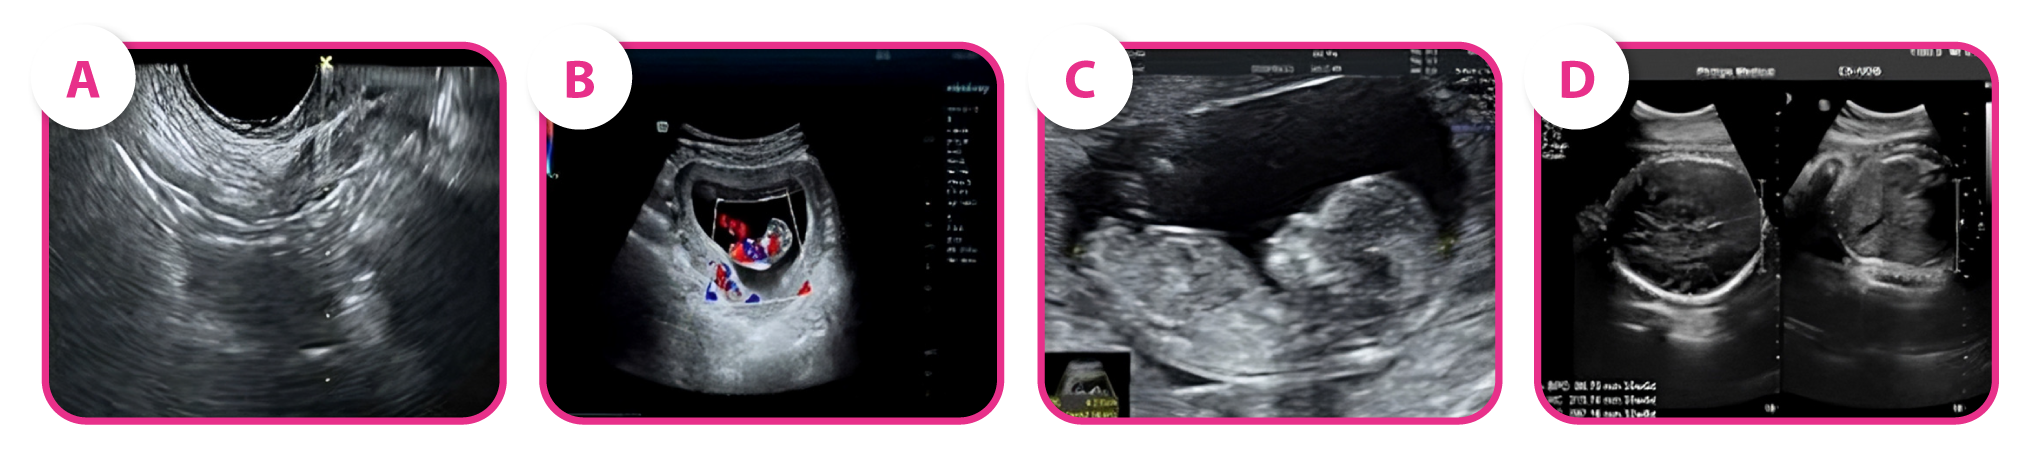

| Objetivo: Investigação da restauração das funções ovarianas por seis meses de 61 pacientes submetidas à reposição hormonal associada a até três infusões intraovarianas de UCMSCs de doadores alogênicos, guiadas por ultrassonografia transvaginal, nas doses de 0,5-1,0 x 10⁷ UCMSCs. |

| Após a primeira infusão, 31,1% das pacientes desenvolveram folículos maduros. Após a segunda e terceira infusão, mais 11,8% e 13,3% das pacientes também tiveram o desenvolvimento folicular, totalizando 56,2% das pacientes. Destas, duas pacientes recuperaram a função menstrual e ocorreram quatro gestações completas. Em conclusão, o estudo mostra que de fato há melhora no crescimento folicular e função ovariana sem eventos adversos graves ou complicações relacionadas ao procedimento e que pacientes com menos de um ano de amenorreia tiveram maior sucesso, sugerindo maior eficácia da terapia em fases mais precoces da doença. |

Gravidez e desfechos neonatais. (B-D) Ultrassom de uma paciente gestante na semana 8 (B), 13 (C) e 32 (D).